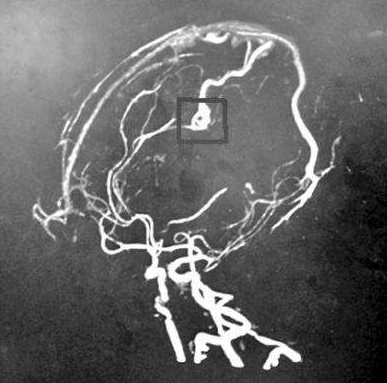

动脉瘤 是血管中有破裂危险的脆弱区域。当动脉瘤位于大脑时,我们称之为脑动脉瘤,脑内动脉瘤,或颅内动脉瘤。脑动脉瘤的形成往往需要很长一段时间,在破裂或破裂之前可能不会...

问: 脑动脉瘤破裂 后会发生什么? 答:脑动脉瘤表明血管中的薄弱区域,经常变大并暗示相应血管的膨胀。相关阅读: 脑动脉瘤破裂出血怎么办? saccular aneurysm 囊状动脉瘤 fusiform an...

颅内动脉瘤,又称脑动脉瘤,是一种脑血管疾病,由于大脑动脉或静脉管壁薄弱,导致血管局部扩张或膨胀。后循环(基底动脉、椎动脉和后交通动脉)的动脉瘤有较高的破裂风险。基底...